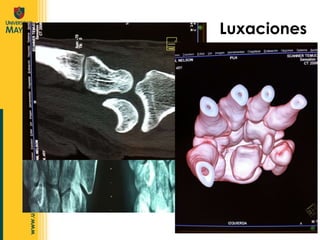

Luxaciones Pérdida completa y estable de la congruencia  de las superficies óseas que forman una articulación. URGENCIA TRAUMATOLOGICA

Luxaciones Subluxación :  Pérdida parci al de la congruencia articular

Dirección: Dorsal, Volar o Lateral. Luxación de Falanges Clasificación de Eaton y Littler de Luxac. Dorsales: I Hiperextensión II Luxación dorsal II Luxación y fractura

Hiperextender la  MTC-F a 90 °  y empujar la base proximal hacia la flexión. Inmovilizar por 2-3 semanas. Luxación de Falanges